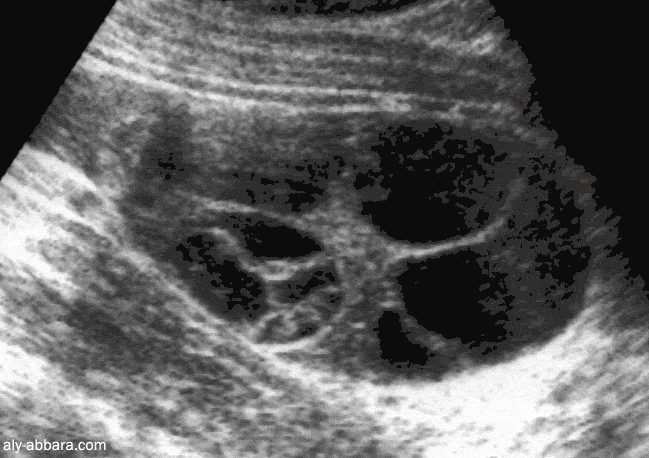

Kyste mucineux de l'ovaire (kyste mucoïde)

Caractéristiques échographiques